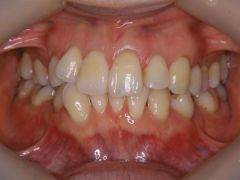

初診時年齢32歳の女性 上顎前歯部の叢生を主訴に来院された。

下顎左側側切歯が先天欠損で、上顎右側第一小臼歯も抜歯されていた。上顎右側小臼歯を抜歯していただき動的治療を行った。下顎が3本切歯であり上下の正中線の合致は困難であるが、下顎歯の抜歯を行わない方針であること、さらに下顎前歯の叢生の改善により歯間弧形空隙(いわゆるブラックトライアングル)が生ずる可能性を説明したが、この方針やリスクに同意が得られたため、上顎左側小臼歯のみを抜歯して動的治療を行った。的治療期間1年10カ月